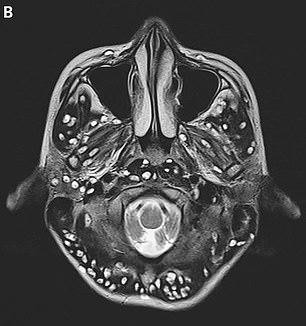

Qua kết quả quét não MRI, bác sĩ nhận thấy có rất nhiều trứng sán ở khắp vỏ não, mắt phải và tinh hoàn phải.

Bác sĩ xác định cậu bị bệnh u nang thần kinh học, được Tổ chức Y tế Thế giới (WHO) định nghĩa là "nhiễm ký sinh trùng ở hệ thần kinh trung ương và do sán lợn Taenia solium gây ra".

Căn bệnh này xảy ra do một loại sán dây có trong thịt lợn, đặc biệt là thịt lợn không được nấu chín, xâm nhập vào cơ thể và "làm tổ" tại não.

Neurocysticercosis là một dạng nhiễm trùng bởi các u nang do ấu trùng của sán dây lợn tạo ra. Đây là những túi chứa ký sinh trùng chưa trưởng thành. Những u này có thể ảnh hưởng đến những bộ phận khác nhau của cơ thể. như hệ thống thần kinh trung ương, cơ, da và mắt.

Khi chúng hình thành trong não được gọi là Neurocysticercosis. Não bị ảnh hưởng có thể gây ra co giật và tử vong. Mức độ tổn thương não trong trường hợp này được so sánh ngang với u xơ thần kinh.